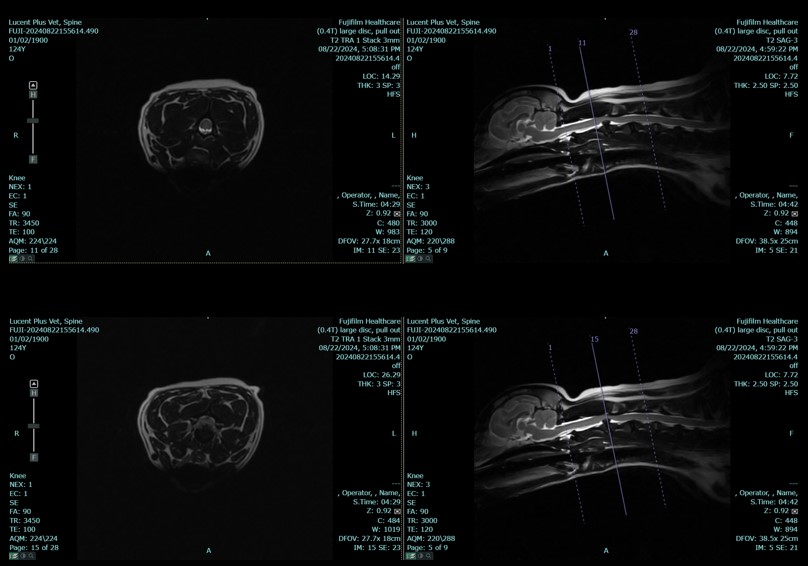

Space saving and wide open APERTO Lucent MRI delivers imaging excellence, affordability, positioning versatility and unmatched patient access. The streamlined open single-pillar design minimizes space requirements. Minimal power demand, helium free technology and air cooling keep operating costs low. Fujifilm dependable capture and processing technologies, supported by expert service, ensure reliable performance while innovative automated imaging shortcuts improve workflow efficiency and image quality.

APERTO Lucent VET’s wide, laterally moving table and wide selection of high-sensitivity coils enable effective imaging across a broad range of animal sizes and body shapes. The open magnet design accommodates support equipment and in-place interventional procedures.

• IP-RECON iterative reconstruction delivers exceptional image quality with faster scan times

Iterative Processing reconstruction (IP-RAPID) reduces noise while maintaining the Signal to Noise (SNR) providing high quality and fast scan times, minimizing the animal’s time on the table and increasing workflow.